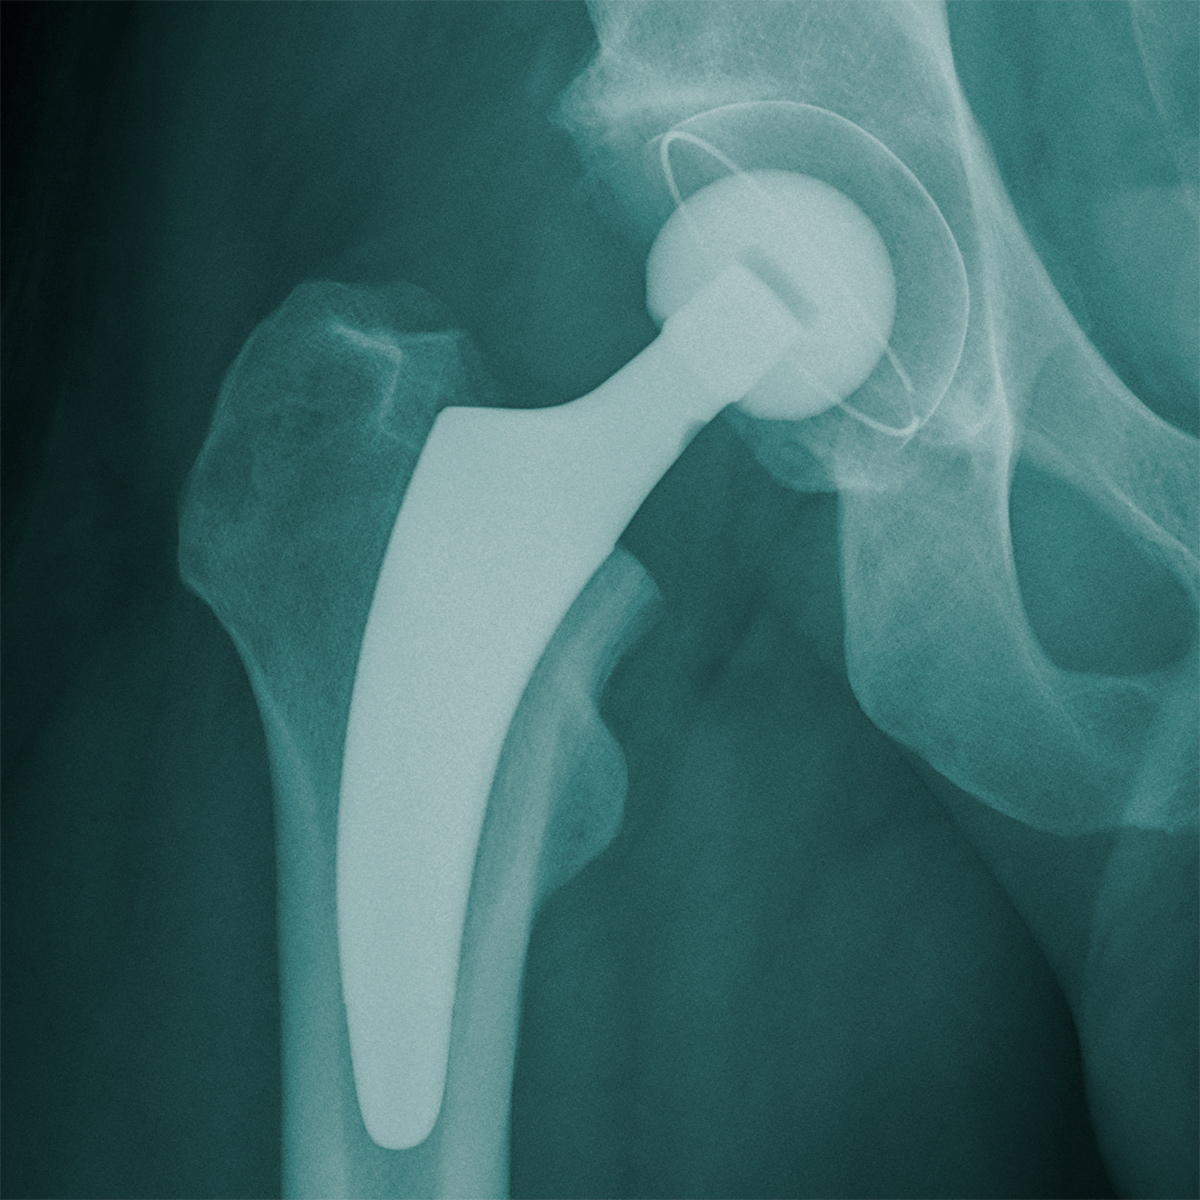

El vástago optimys se desarrolló para permitir la reconstrucción individual de la anatomía del paciente. La estructura guía durante la implantación es la curvatura media del fémur con el objetivo de restablecer el centro de rotación y la lateralización (offset), con independencia de la situación inicial (posición en varo o valgo del cuello femoral). 1, 2

La filosofía del vástago optimys sigue la curvatura media del fémur (arco calcar). De este modo, el vástago se puede adaptar a las condiciones anatómicas del paciente con el objetivo de reconstruir el offset. 1, 2 Con la ayuda del marcado diseño de triple cono se persigue logar una buena estabilidad primaria a fin de minimizar el riesgo de hundimiento de la prótesis después de la intervención quirúrgica. 3, 4, 5 Además, con la ayuda del aerosol de plasma de titanio con recubrimiento de fosfato de calcio se favorece el desarrollo del hueso en el vástago.

El sistema incluye una gama abarcable de implantes con 12 tamaños para la versión estándar y lateral.